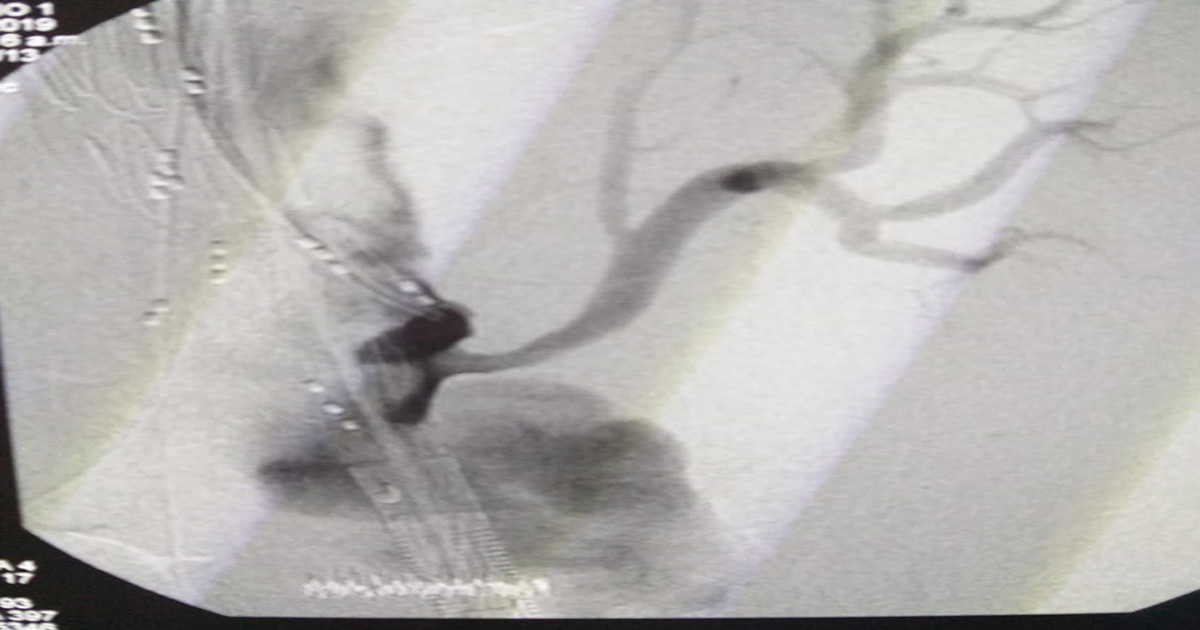

Durante la junta quirúrgica, se analizan y estudian los diferentes apoyos diagnósticos hechos en la paciente y se define un manejo endovascular con prótesis toracoabdominal más una revascularización y con ello evitar el alto riesgo de ruptura de la arteria.

Posteriormente, se hace exploración arteria bilateral inguinal y junto a la arteria axilar se pasan dos introductores para que guías hidrofílicas más dos landerquist dan paso a la prótesis ‘T Branch de Cook’ el cual es liberado en la aneurisma y así reducir la inflamación arterial. Al finalizar, se hace canulación de arterias como la abdominal y renal, entre otras ramificaciones del sistema circulatorio.